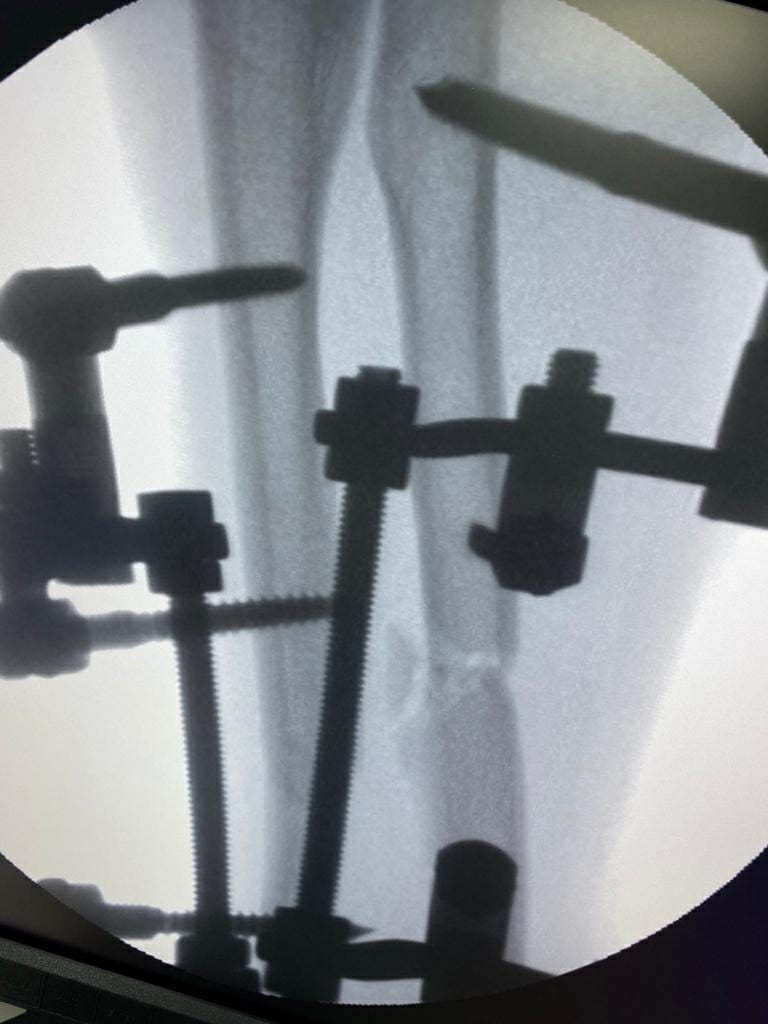

Коррекция при переломах костей после травм